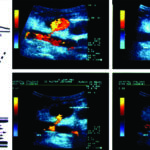

La Ecografía es el método de elección para el diagnóstico inicial, no solo por su amplia disponibilidad sino porque permite rápidamente la realización de mediciones en el plano longitudinal, anteroposterior y transverso (Fig. 26). Está indicada para la realización del screening del aneurisma de aorta abdominal en pacientes mayores de 65 años y con factores de riesgo.

La técnica de evaluación del aneurisma de aorta abdominal incluye mediciones, las cuales deben realizarse desde los bordes externos de la misma. En el plano longitudinal se examina la aorta desde el diafragma hasta la bifurcación ilíaca, y se miden el diámetro anteroposterior y la longitud del aneurisma. En el plano axial se mide el diámetro transverso. Para categorizar el tipo de aneurisma se examina la relación y distancia del aneurisma con respecto a la emergencia de la arteria mesentérica superior, de las renales y de la bifurcación ilíaca. Se examinan las arterias ilíacas y se mide su diámetro para determinar si están comprometidas. Las arterias ilíacas primitivas tienen un diámetro anteroposterior normal de hasta 11 mm (Fig 27).

El DC permite una evaluación más exhaustiva, con la cual no solo podemos determinar con precisión los límites de la dilatación aneurismática sino que también hace posible percibir la turbulencia en el flujo dentro de la misma (Fig. 28).

Al realizar la evaluación ecográfica, el especialista no debe dejar pasar por alto la presencia de trombosis mural o trombos de flotación libre en su informe, lo cual en una segunda etapa estará íntimamente relacionado con el abordaje terapéutico del paciente (Fig. 29).

Se debe tener en cuenta la posible asociación entre los aneurismas de la aorta abdominal y aquellos presentes en las arterias ilíacas, torácicos, femorales y poplíteos (Fig. 30), los cuales ocurren en un 50%, 12% y 15% de los casos, respectivamente (20).